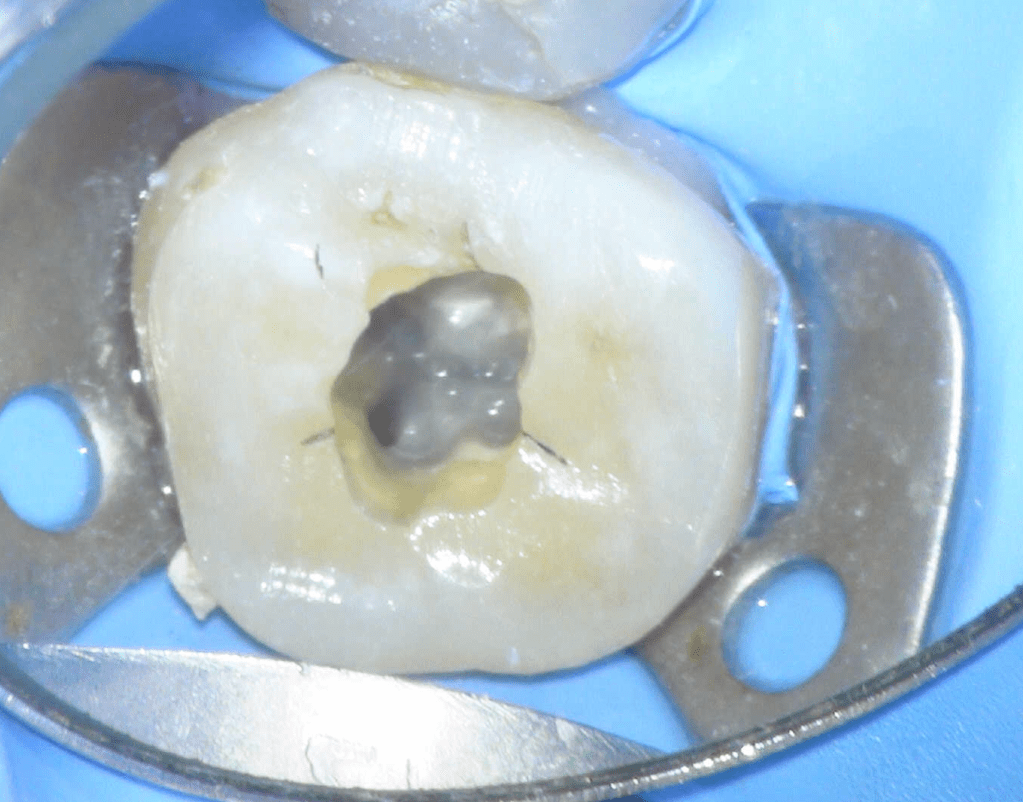

Fisura, remoción amalgama para explorar